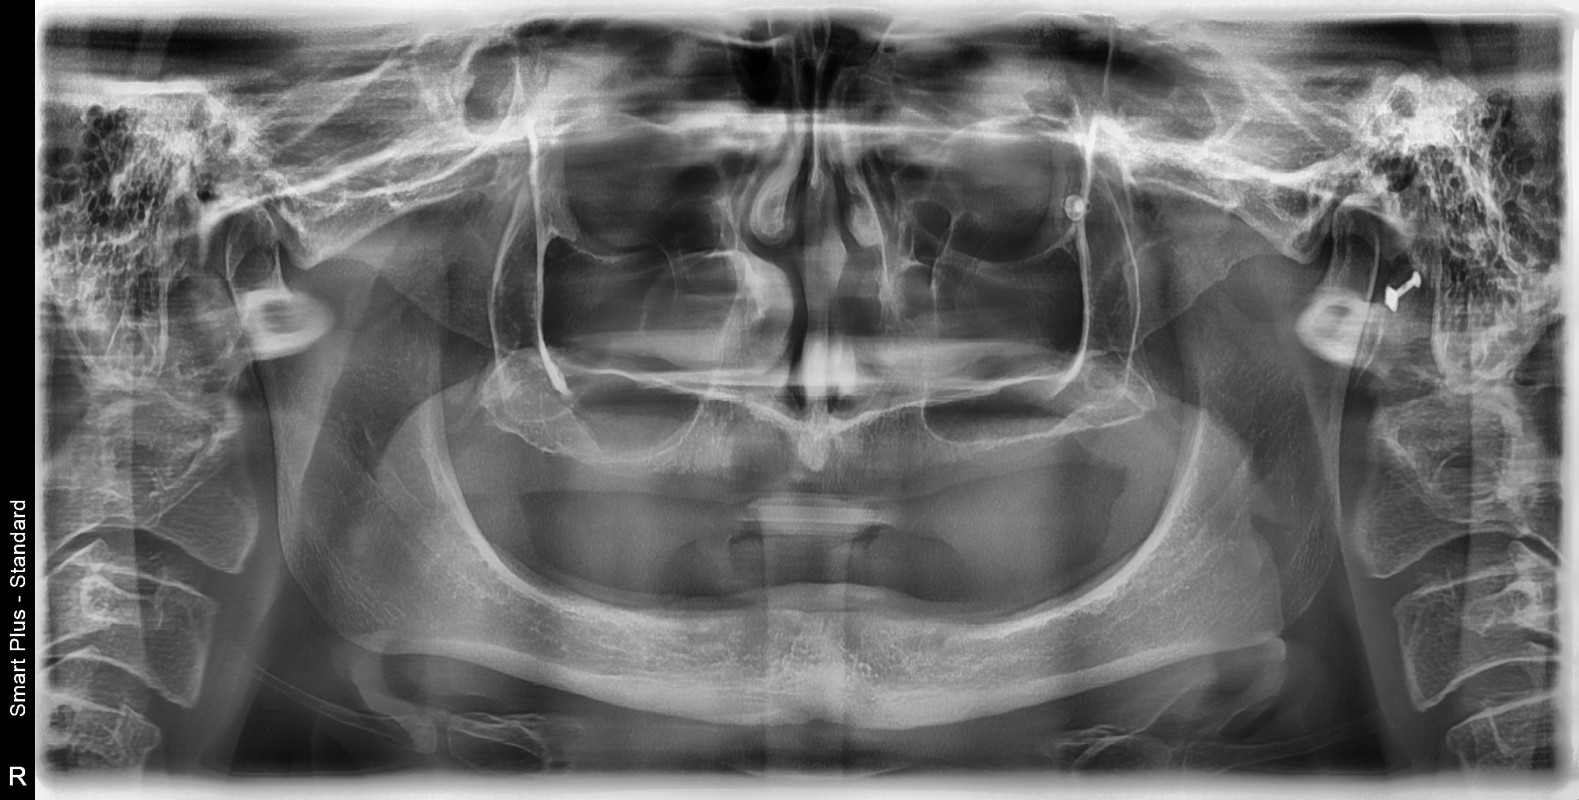

This is a little hard for me to share, but I’m reaching out because I truly need help. I’m currently facing some major dental issues that have really affected my confidence, my ability to smile, and even how I feel day to day. Unfortunately, the dental work I need isn’t covered by my insurance here in Delaware, and I’ve been told the full cost will be around $5,000 out of pocket. I’ve been doing everything I can to save up, but it’s been tough. This situation has really taken a toll on my self-esteem — something as simple as smiling or talking with people has become something I avoid. I just want to feel like me again. If you’re able to help in any way, even by sharing this post, it would mean the world to me. Every dollar brings me one step closer to smiling with confidence again and feeling like myself. Thank you for taking the time to read this and for any kindness you can offer.